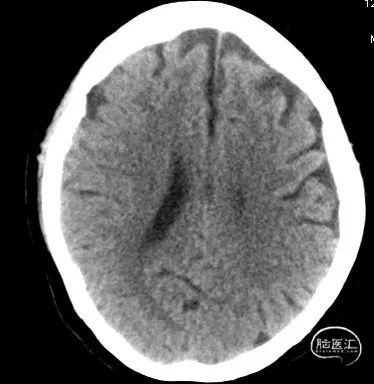

急诊颅脑CT+CTA:多发腔梗,ASPECTS评分:8分;CTA示右侧M1闭塞。

急诊颅脑CT+CTA

急诊颅脑CT+CTA:无脑出血,ASPECTS评分:7分;CTA示右侧M1闭塞。